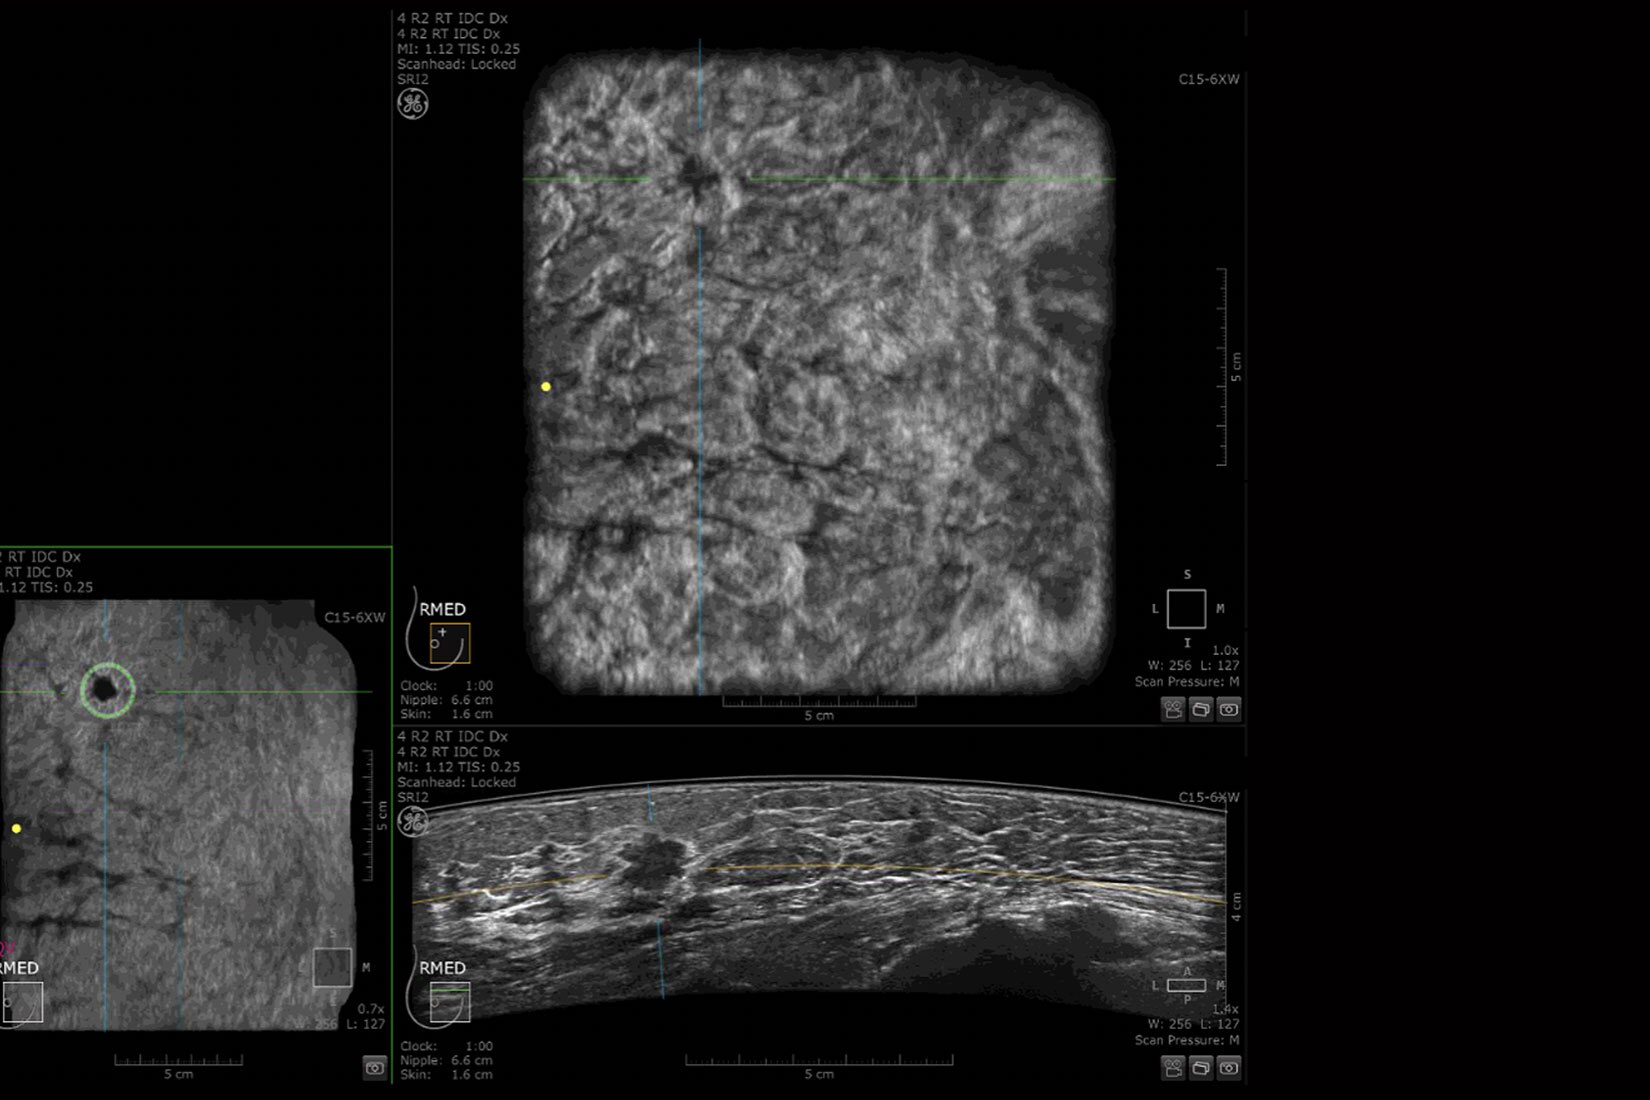

En zorlu departman programlarını bile SIGNA™ Hero ile verimli hale getirin. AIR™ Koiller ve AIR™ Recon DL, genel klinik pratiğin bir parçası olarak meme ve prostat kanseri incelemesi gibi alanlarda uçtan uca klinik çözümlere sahip olmanızı sağlar.